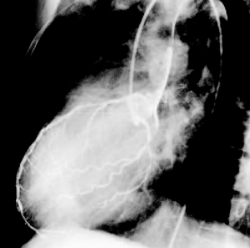

FIGURE. No caption a... - Click to enlarge in new windowFIGURE. No caption available.